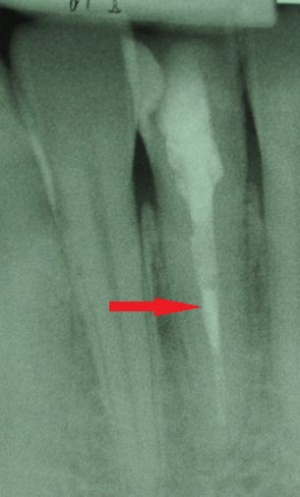

REGENERATION DER DENTALEN PULPA

Wurzelkanalbehandlung heute Der menschliche Zahn ist, bei genauerer Betrachtung, ein komplexes kleines Organ, zusammengesetzt aus verschiedenen Hart- und Weichgeweben. Die mineralisierten Gewebe – Schmelz, Dentin…

ONE FILE ENDO

RECIPROC® ist die wohl bedeutendste Neuentwicklung seit der ersten Nutzung von Nickel-Titan Instrumenten zur Aufbereitung von Wurzelkanälen. Anders als bei rotierenden NiTi-Systemen mit aufwändigen Instrumentensequenzen…